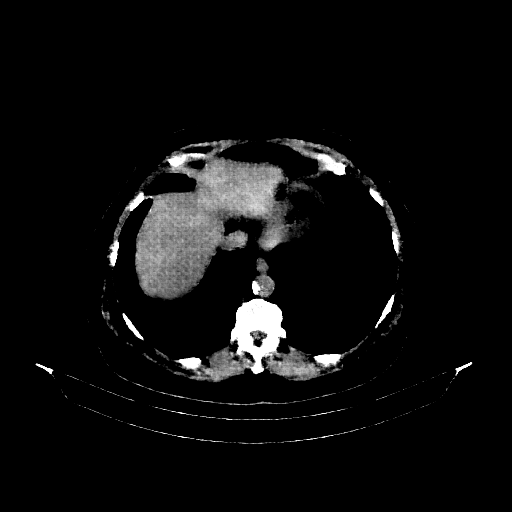

Generated VENOUS CT scan (A→B translation)

Full window (WL 1023.5, WW 4095 β†’ Low βˆ’1024, High +3071)

Actual HU range: [-876.3, 832.7]

Lung window (WL -600, WW 1500 β†’ Low βˆ’1350, High +150)

Actual HU range: [-876.3, 150.0]

Mediastinum window (WL 40, WW 400 β†’ Low βˆ’160, High +240)

Actual HU range: [-160.0, 240.0]